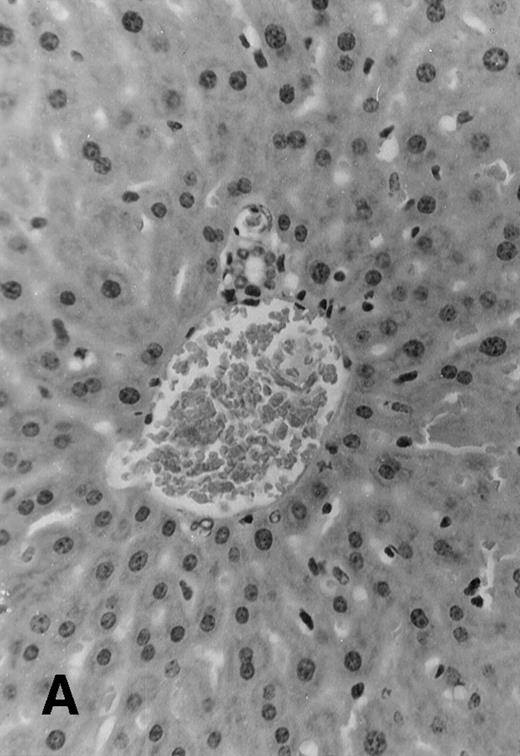

Five of 6 (83%) of (SJL × C57.BL6) F1 mice that received 1 × 106 TCD parental SJL BM cells survived to day +51 posttransplant. These mice appeared healthy and active, with a median weight of 35 ± 1.4 g. All 7 F1 mice that received TCD SJL BM and 30 × 106 irradiated (7.5 Gy) SJL splenocytes survived without evident clinical signs of GVHD. These mice appeared healthy and had a median weight of 35 ± 1.8 g. Seven of 8 (87.5%) F1 mice, which received a combination of SJL TCD BM and 30 × 106 nonirradiated SJL splenocytes, survived to day +51. However, these mice were wasted with a median weight of 24.4 ± 3.4 g and had patchy alopecia and diarrhea (Table 2). Necropsy of all surviving animals at day +51 showed lymphoid hypoplasia among recipients of nonirradiated allogeneic splenocytes. These animals had spleens with mean weights of 30 ± 20 mg compared with normal spleen weights among recipients of TCD BM alone (160 ± 30 mg, P < .0001) or TCD BM plus irradiated allogeneic splenocytes (150 ± 30 mg,P < .0001). Histology examination of samples of skin, liver, and intestine from transplanted mice showed variable degrees of lymphocytic infiltration of the liver, epithelial thickening, and autolysis and sloughing of intestinal epithelium. Evidence for acute GVHD was minimal among recipients of TCD BM alone (Fig 4A) or irradiated allogeneic lymphocytes (Fig 4B). Histologic examination of the liver from recipients of nonirradiated allogeneic splenocytes showed acute and chronic inflammation of the portal tract (Fig 4C) and focal hepatic parenchymal injury. The hepatic GVHD score (on a scale of 0 to 3) and overall GVHD score (on a scale of 0 to 6) for each animal was calculated according to the Materials and Methods section. Recipients of nonirradiated splenocytes had higher GVHD scores than the group that received irradiated splenocytes and the group that received TCD BM alone (Table 2).

Histology sections of liver from recipients of MHC mismatched TCD BM and allogeneic splenocytes. Sections of liver from (C57.BL6 × SJL) F1 mice that were transplanted on day 0 with 1 × 106 SJL TCD BM cells alone (A) or TCD BM in combination with 30 × 106 irradiated (7.5 Gy) splenocytes from SJL donors (B) or with 30 × 106 nonirradiated splenocytes (C). Mice were euthanized at day +51 and samples of liver tissue were fixed in 10% formalin, embedded in paraffin, and sections were stained with hematoxylin and eosin. Original magnification is ×165 in all 3 photomicrographs.